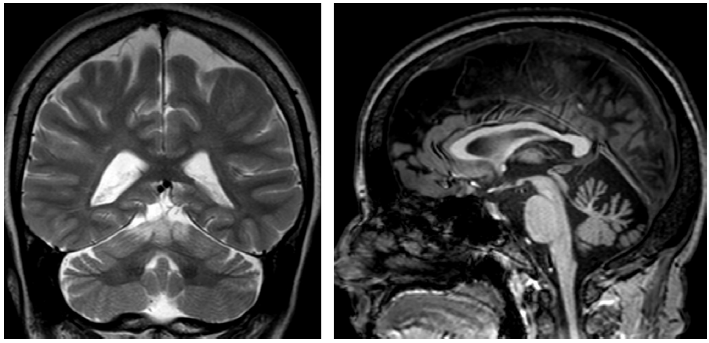

图3 副肿瘤性小脑综合征相关的广泛小脑萎缩。左:头颅MRI T2加权序列冠状位图像。右:头颅MRI T1加权序列矢状位图像。

图9 头颅MRI显示痉挛性共济失调(ARSACS

)相关的小脑萎缩。左:头颅MRI T2加权序列冠状位图像; 右:头颅MRI T1加权序列矢状位图像。

图10 线粒体疾病相关的小脑萎缩。图为头颅MRI T1加权序列矢状位图像。